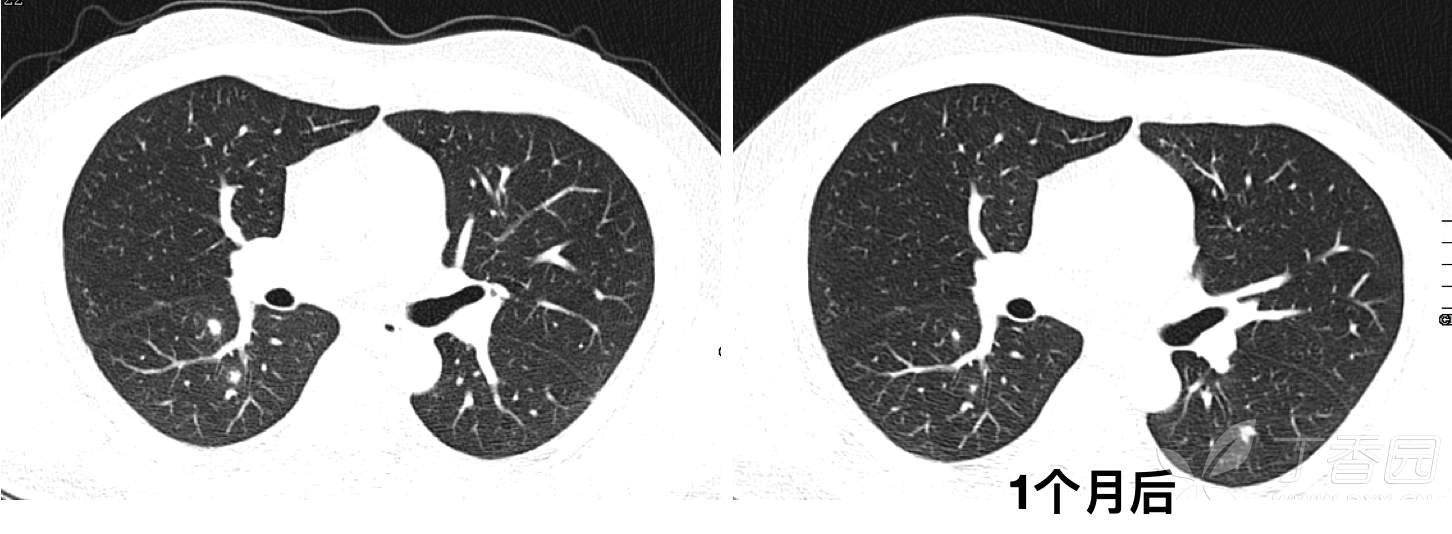

CT发现右肺多发结节影,初步诊断为肺炎,予莫西沙星口服治疗2周,1个月后复查CT如下: